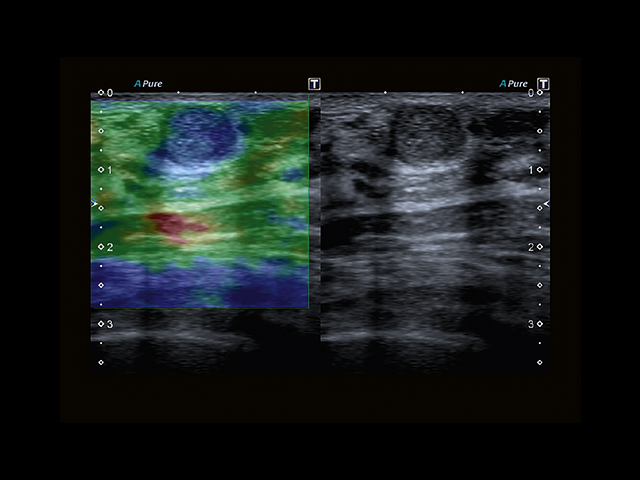

Обновленная версия легендарного УЗ-сканера. Стационарный аппарат экспертного класса Aplio 500 Toshiba NEW, визуализирует анатомические структуры в высоком разрешении. Модель позволяет выявить микрокальцификаты, новообразования, нарушения в работе сердца, сосудов и мышц. Присутствует функция виртуальной эндоскопии, 4D-сканирования, эластометрии тканей, УЗИ с контрастированием. За повышение качества изображения отвечают технологии ApliPure и Superb Microvascular Imaging. Первая задействует возможности пространственного и частотного кодирования, формирует цельный визуальный ряд с сохранением клинических маркеров. Вторая улучшает отображение микрососудистого русла, используя доплеровский эффект. Модель оснащена 21-дюймовым монитором, имеет 4 активных порта. Возможно подключение педиатрических, интраоперационных, лапароскопических и чреспищеводных датчиков.

• MicroPure. Высокотехнологичное решение в области выявления микрокальцификатов – маркеров новообразований злокачественного типа. Маркеры идентифицируются путем изучения затененных изображений целевого участка. Микрокальцификаты отображаются в виде белых пятен.